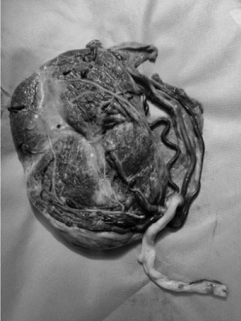

Uma secundigesta, com um parto normal anterior e idade gestacional de 36 semanas e dois dias, deu entrada no pronto-atendimento obstétrico com queixa de sangramento vaginal em grande quantidade há quarenta minutos. Refere que a hemorragia ocorreu “do nada”, tendo início após um “acesso de tosse”. Nega dor abdominal. Realizou seis consultas de pré-natal, com todos os exames dentro do limite da normalidade. Nega antecedentes pessoais de comorbidades. Ao exame de entrada, descorada +/4+, PA de 90 x 50 mmHg, FC de 101 bpm, altura uterina de 33 cm, ausência de dinâmica uterina, tônus uterino normal e BCF de 101 bpm. Especular mostrando grande quantidade de coágulos na vagina e sangramento ativo por orifício externo do colo. Foi encaminhada para cesariana de emergência. A foto abaixo corresponde à placenta, após dequitada.